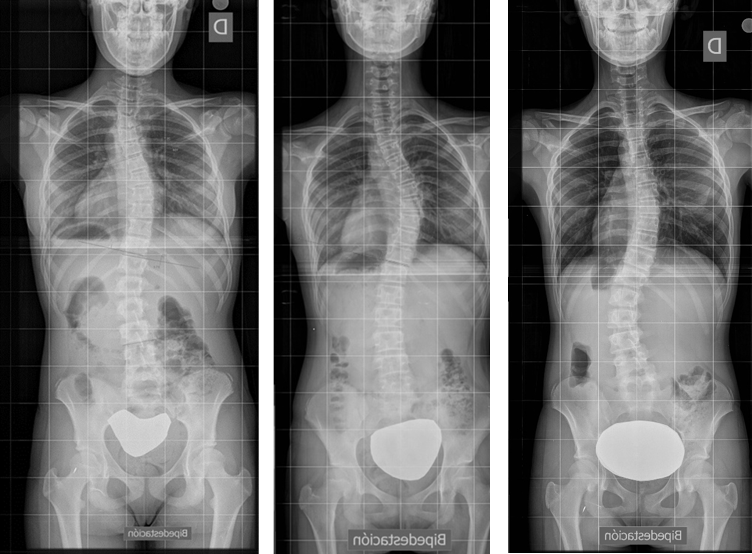

Todo esto explica la repercusión estética (signo de Adams) y pulmonar de la escoliosis. Y esto nada más, define una escoliosis. En la Figura 11 se puede observar una grave escoliosis con una perfecta simetría en los hombros, pelvis y caderas.

Figura 11. Simetría en los hombros pelvis y caderas con una grave escoliosis dorsal. Mostrar/ocultar